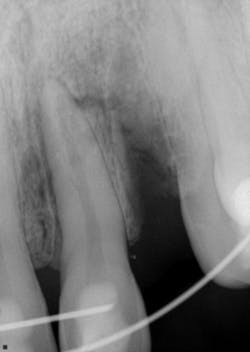

Twelve days later, the patient returned with the following assessment and treatment (figure 4):

- Overall, the patient was feeling better, with reduced swelling in all soft-tissue areas.

- Chief concern: His bite was off. This was adjusted.

- Cold testing: No response with No. 9 and slight delay with No. 8.

- Tooth appeared more stable within the alveolus; the splint was removed between Nos. 8 and 9, but not from canine to canine.

- It was recommended that we commence with endodontic treatment on No. 9 and maintain a watch on No. 8 for any irreversible changes.

- Tooth No. 9 was opened up; the pulp was necrotic. The chamber was cleaned out, irrigated, and calcium hydroxide medicament was placed. It was recommended that we change out the dressing two to three more times over the course of the next few months, so stabilization of the tooth could continue and a better prognosis could be determined.

Figure 4